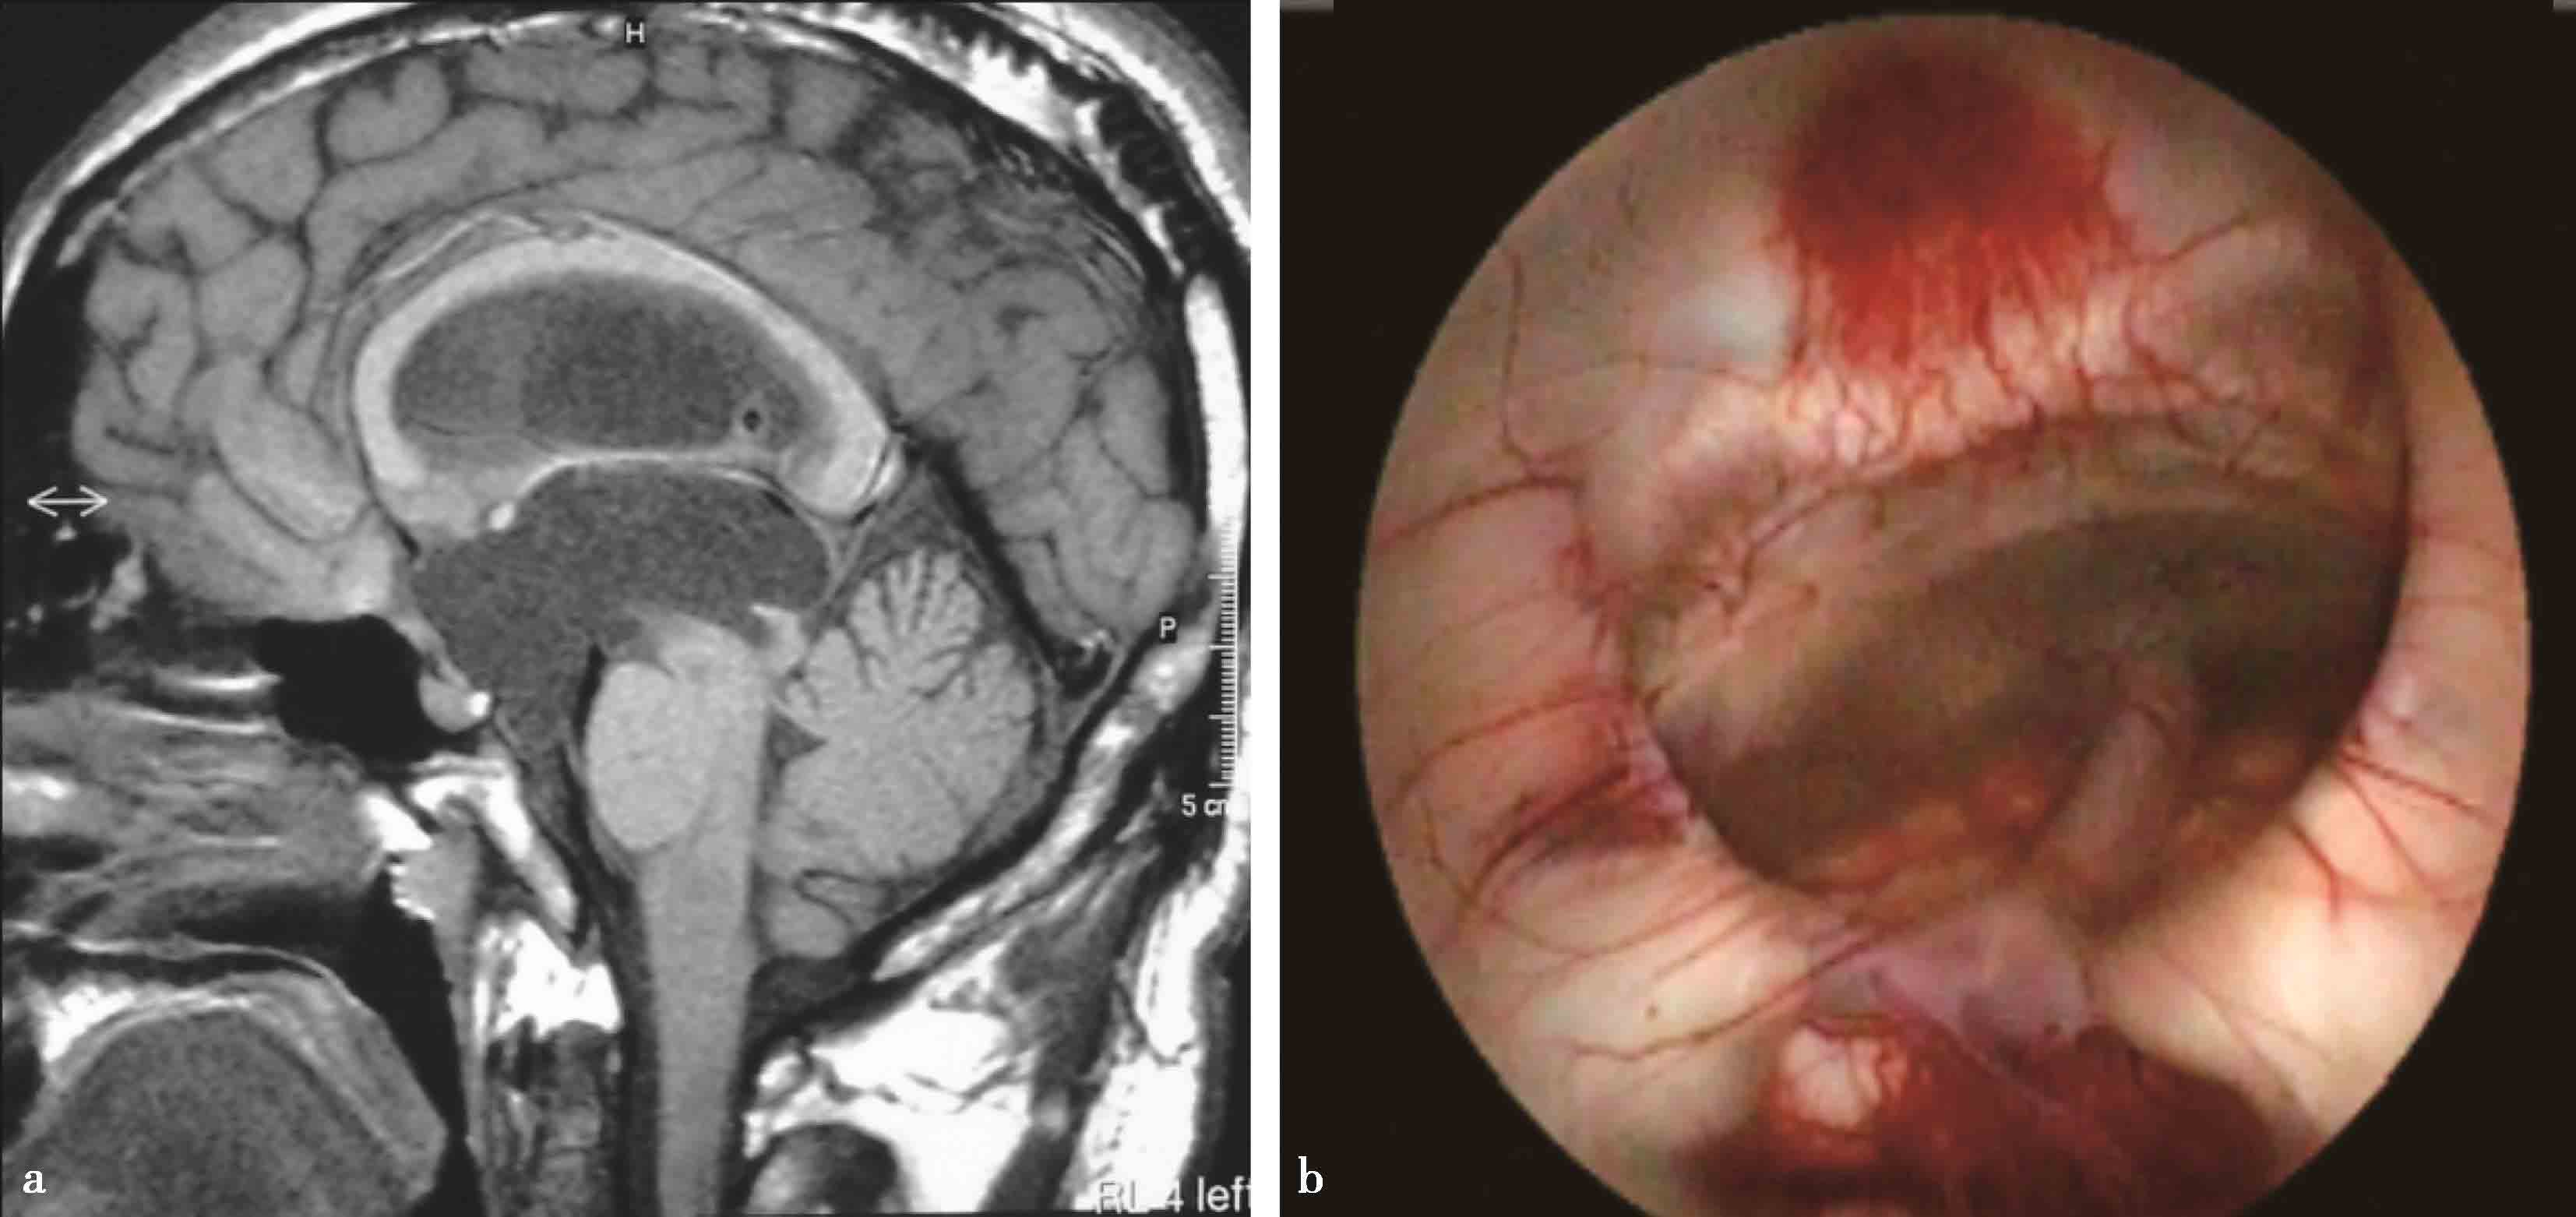

图3-1-2-11 脑积水合并Chiari畸形

a.术前MRI矢状位片示脑积水,小脑扁桃体下疝;b.第三脑室底造瘘术后1周,MRI矢状位片示小脑扁桃体下疝减轻